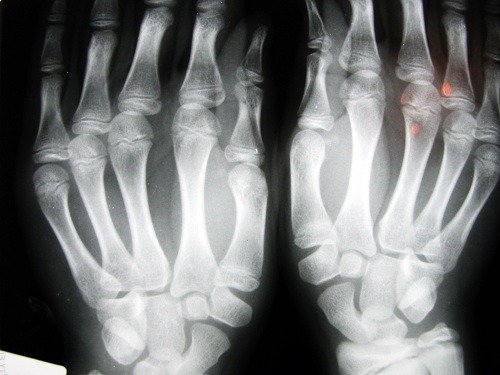

Kırıklar sıklıkla bileklerde ve kalça omurgasında oluşur. Bu en ciddi kırıktır çünkü acil olarak cerrahi müdahale yapılması gerekir ve hastanın sağlığı açısından ciddi sonuçlar doğurabilir.